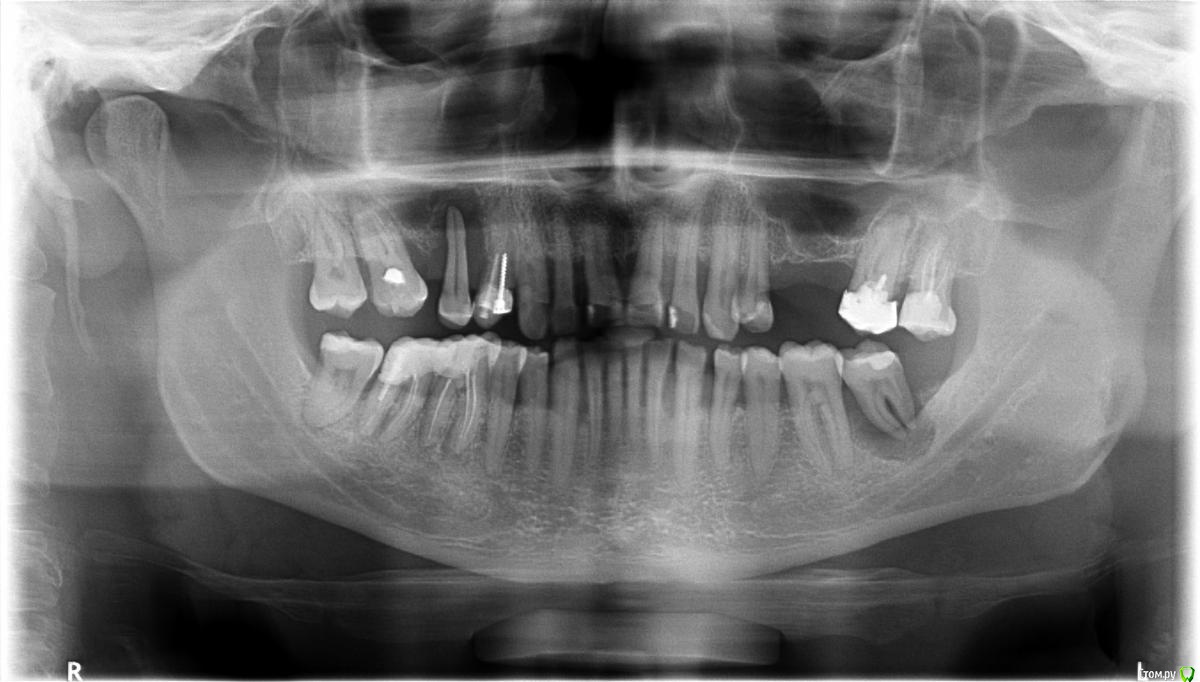

chervoncevdaniil Опубликовано 5 ноября, 2016 Поделиться Опубликовано 5 ноября, 2016 (изменено) 15,37 на удаление.27-перелечивание корневых каналов16-эндолечение14 и 16 нужно смотреть очно,можно ли их использовать под опорыВарианты протезирования:Синус-лифтинг и имплантация в области 25 и 26 либо мостовидный протез 24-27 Правая сторонаМостовидный протез 13-14-17(при условии адекватного количества твердых тканей 14 и 17 зубов),либо имплантация в проекции 15-16+синус лифтингТут панорамного снимка мало,нужно смотреть наличие места под коронки Изменено 5 ноября, 2016 пользователем chervoncevdaniil Ссылка на комментарий

M@estro Опубликовано 5 ноября, 2016 Поделиться Опубликовано 5 ноября, 2016 (изменено) 15,37 на удаление.27-перелечивание корневых каналов16-эндолечение14 и 16 нужно смотреть очно,можно ли их использовать под опорыВарианты протезирования:Синус-лифтинг и имплантация в области 25 и 26 либо мостовидный протез 24-27 Правая сторонаМостовидный протез 13-14-17(при условии адекватного количества твердых тканей 14 и 17 зубов),либо имплантация в проекции 15-16+синус лифтингТут панорамного снимка мало,нужно смотреть наличие места под коронки 17 - ый, 1.6 удален давно. Мой вариант : 1) удаление 1.5, 1.4, 2.8 ? 3.7 (!) ? 2) перелечивание 2.7, 4.7 ,4. 6, протезирование одиночными коронками.3) качественная пародонтологическая помощь и курация.4) протезирование Мостовидные протезы при такой убыли костной ткани? Если бюджет ограничен - то бюгельный протез с кламмерной фиксацией. Изменено 5 ноября, 2016 пользователем M@estro Ссылка на комментарий